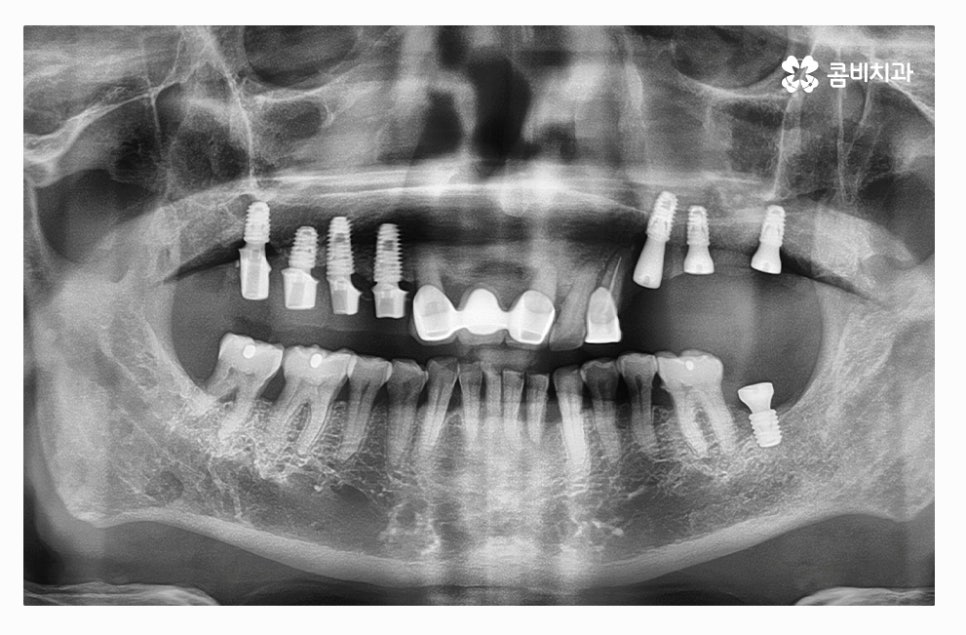

오늘 보여드릴 사례의 경우 치주질환과 염증으로 인해서 윗니를

모두 잃게 되어 전체임플란트 시술을 하게 된 사례라고 할 수 있는데요.

치아를 발치한 후 잇몸 뼈의 상태를 보면 잇몸이 내려앉아 있고

잇몸 뼈가 부족해진 상태라는 것을 알 수 있는데요.